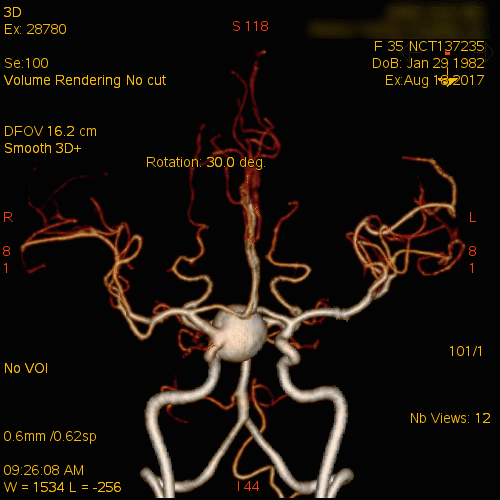

术前CTA示巨大右侧颈内动脉眼动脉段动脉瘤

CTA矢状位重建示动脉瘤下部位于前床突下